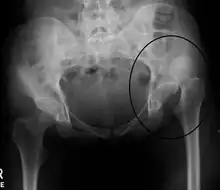

| X-ray showing a joint dislocation of the left hip. | |

Typically, people with hip dislocations present with severe pain and an inability to move the affected leg.[1][4] Diagnosis is made by physical exam and plain X-rays of the hips. A CT scan is recommended following reduction to rule out complications. Complications include osteonecrosis, femoral head fractures, and posttraumatic osteoarthritis.[12][13]

An anterior-posterior (AP) X-ray of the pelvis and a cross-table lateral X-ray[24] of the effected hip are ordered for diagnosis.[4][5][16] The size of the head of the femur is then compared across both sides of the pelvis. The affected femoral head will appear larger if the dislocation is anterior, and smaller if posterior.[7] A CT scan may also be ordered to clarify the fracture pattern.[20]